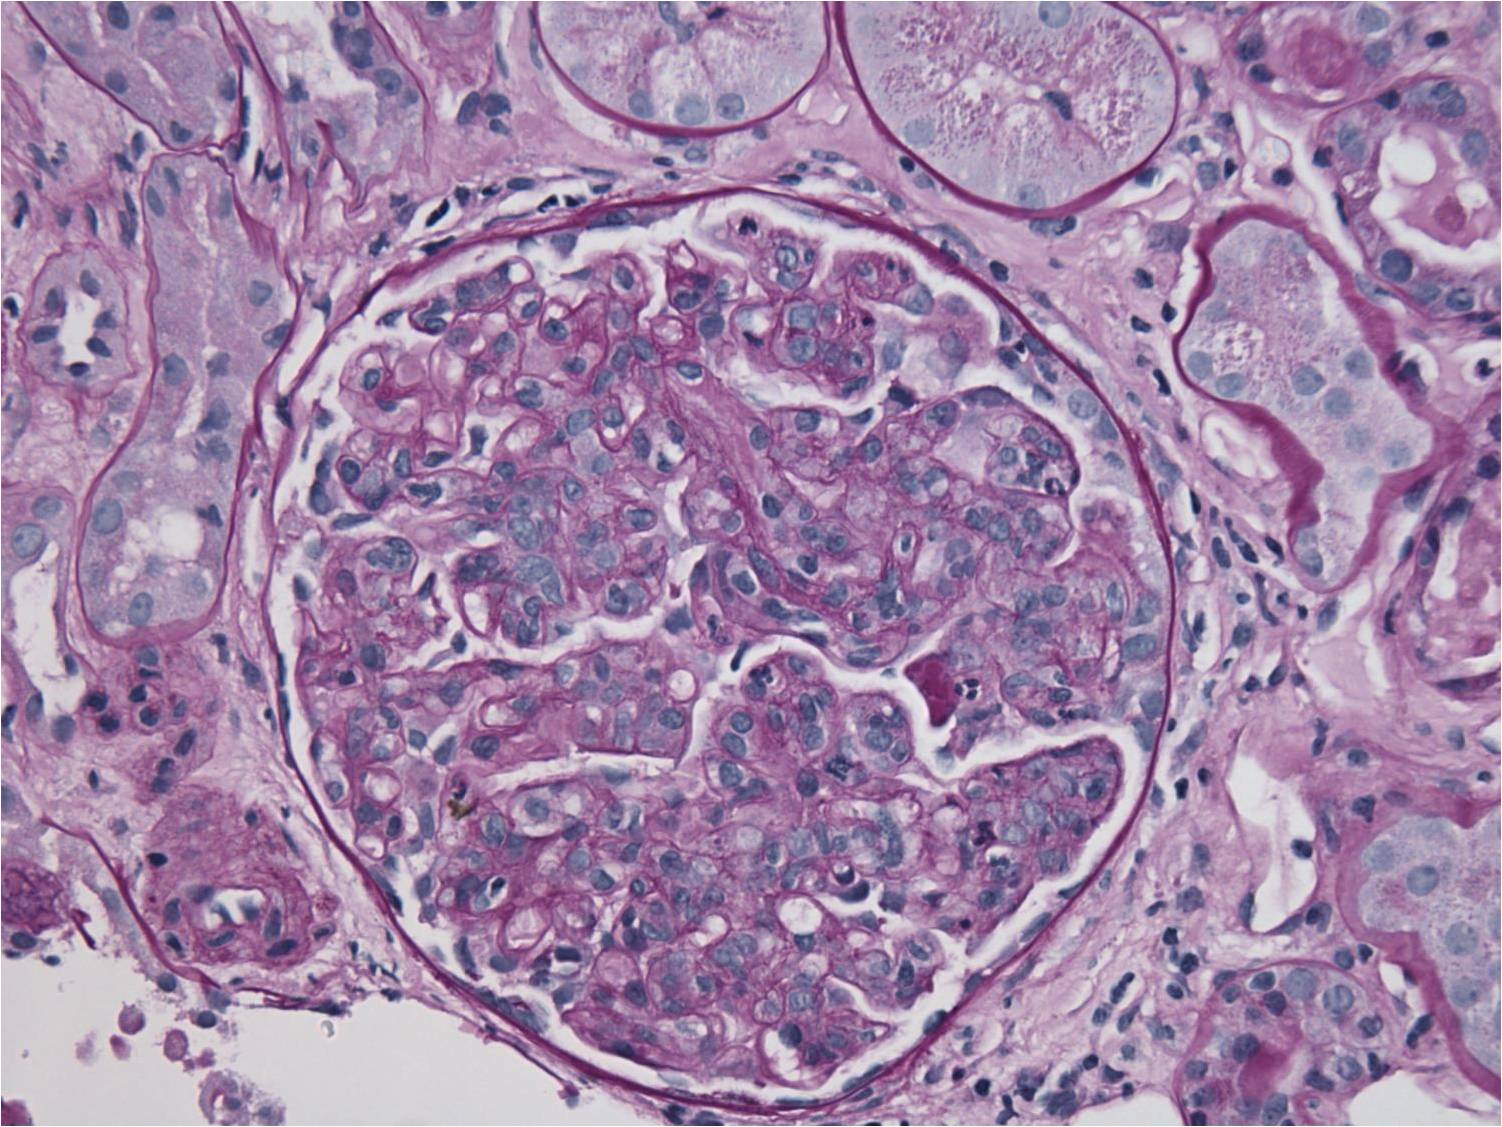

Two glomeruli with diffuse hypercellularity of the tuft. There is minimal interstitial inflammation

The infiltrating cells in the glomerular capillaries are predominantly mononuclear cells with isolated neutriphils.